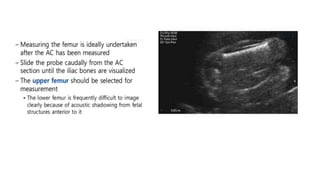

Femoral Length

FL